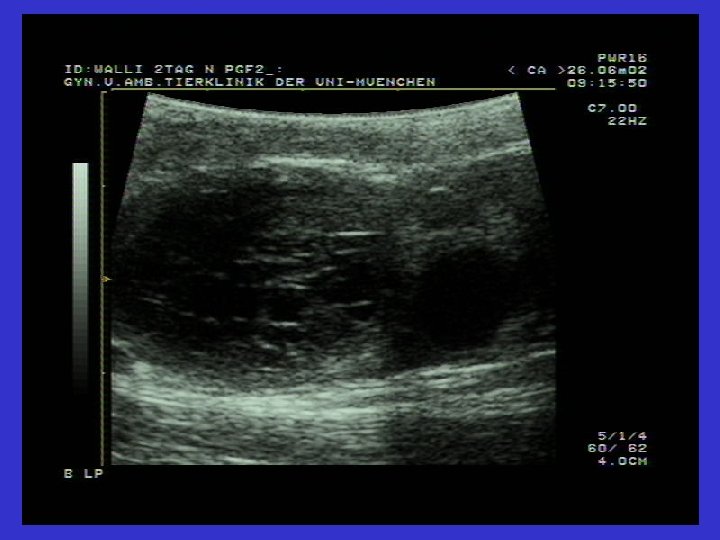

UTERUSTAN KÖKEN ALAN OVARYUM FONKSİYON BOZUKLUĞU Corpus luteum psödogravididatis (Corpus luteum persistens) Tanımı: Corpus luteum persistenz, corpus luteumun ovaryum üzerinde kalması gereken fizyolojik sürenin üzerinde kalması durumudur (saptadıktan sonraki 11 -14. günde yeniden yerinde). Oluşumu, önemi ve etiyolojisi: Endometritis veya pyometra olgularında PGF 2 endometriyumdan salınmaz. Uterus içeriği patolojik olsada kendi tarafından korunuyor ise, corpus luteum psödogravididatis (Kalıcı korpus luteum) gelişir. Ayrıca tohumlama sonrası gelişen embryonik ölümlerde de C. L. -Persistenz oluşur. Tanı: Sürekli kontrollerde C. l. aynı ovaryumda 21 günün üzerinde saptanırsa Progesteron testi (iki kez 14 gün aralıkla yapılan ölçümde 2 ng/ml ve üzeri= Yani iki kez yüksek) Ultrasonografik Cl bulguları

C. l. persistens (pseudograviditatis) 21 günün üzerinde persistenz C. l. Aynı anda gözlenen Endometritis (veya diğer Uteropatiler)